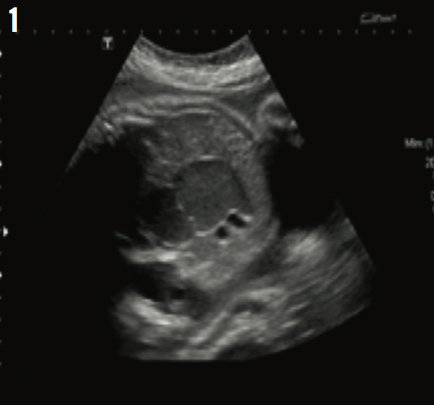

Anshu Kumari, MD; Magda Mendez, MD, FAAP; Sandra Camacho, MD; Amir Navaei, MD

Echogenic bowel has been defined as bowel of similar or greater echogenicity on ultrasonography than surrounding tissues, such as liver, bones, and lung.